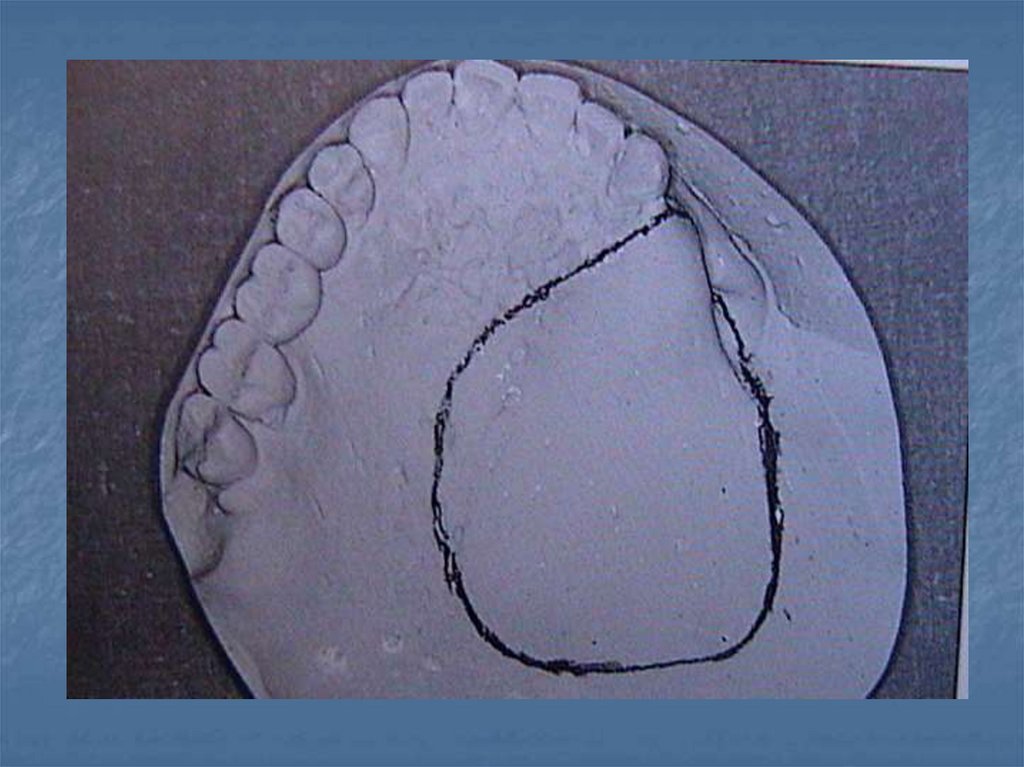

Obturatörleri Etkileyen Kuvvetler-2

premaksillayı da içine